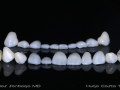

As Facetas Cerâmicas (lentes de contacto dentárias ou laminados), permitem corrigir da maneira mais estética e conservadora possível, problemas de forma e tamanho, côr e posição dos dentes, bem como substituir restaurações antigas e inestéticas.

São aderidas químicamente ao esmalte dentário de uma forma permanente, com o objectivo de melhorar a estética dos nossos pacientes.